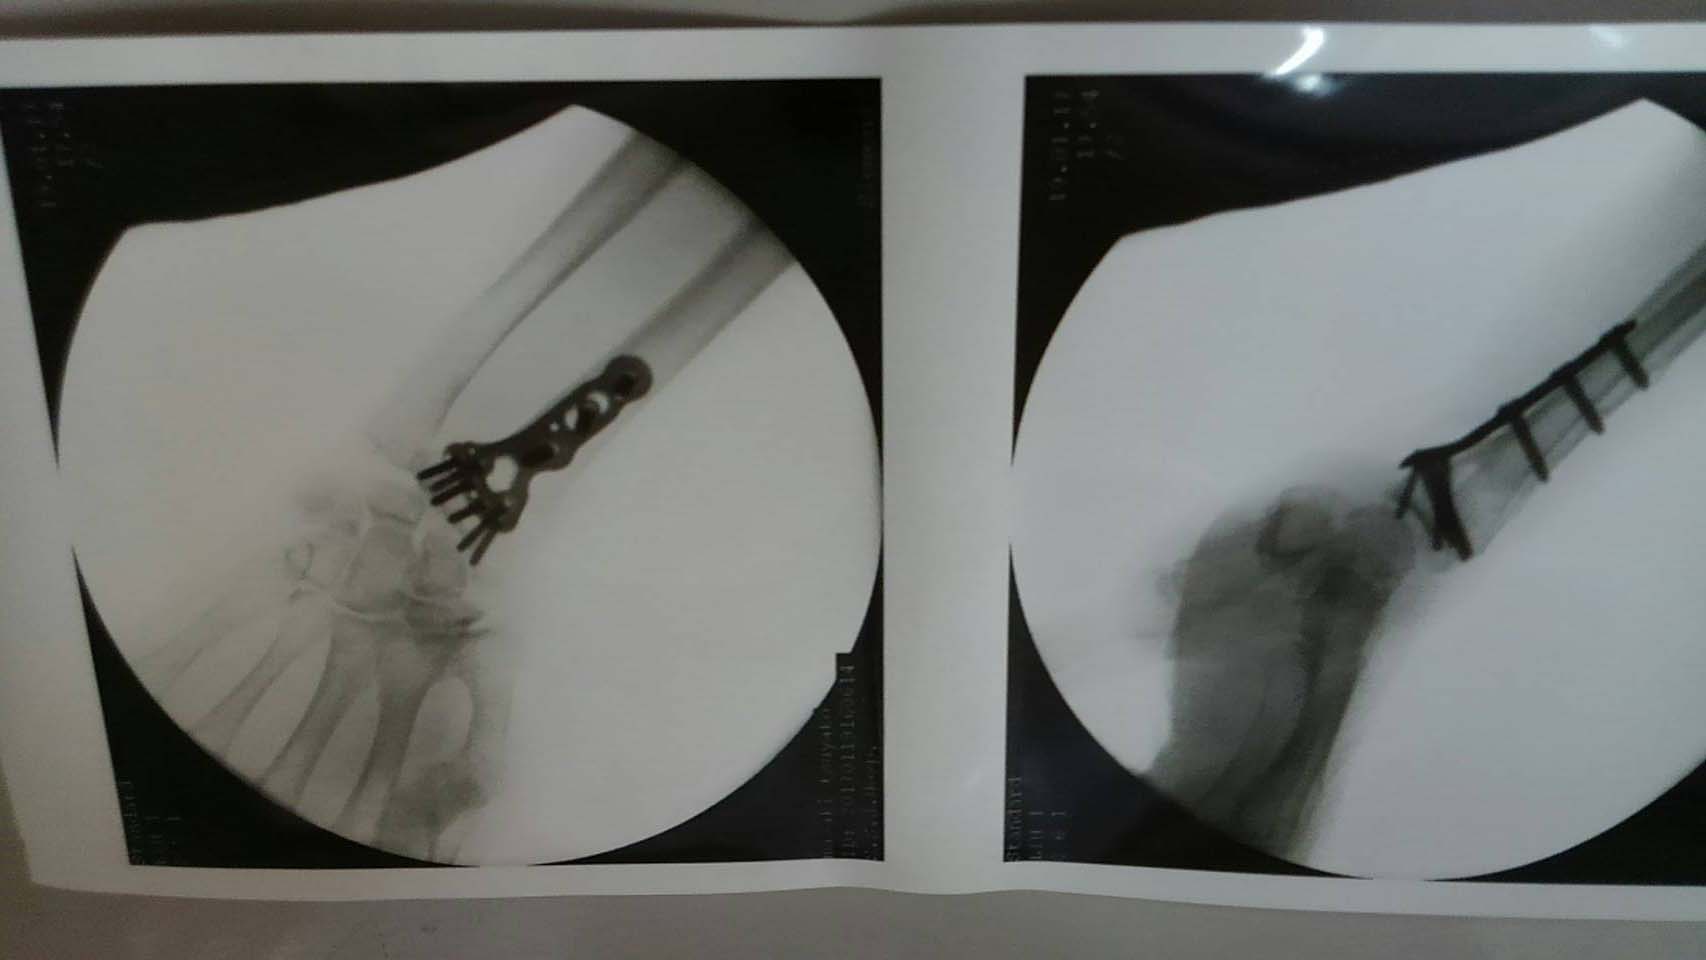

札幌循環器病院 村越先生 右膝人工関節置換手術

札幌循環器病院 左足人工関節置換手術